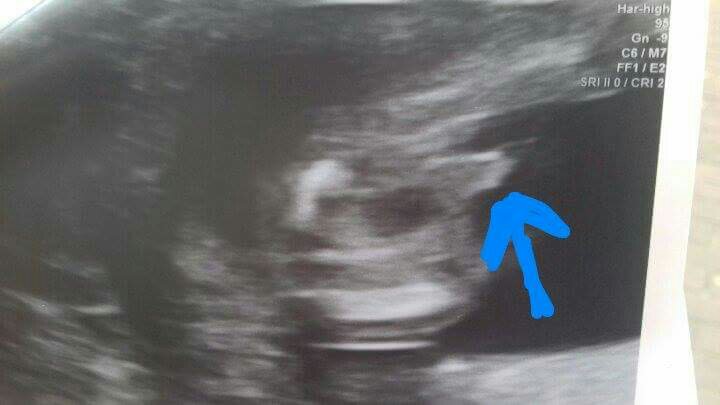

Zobacz załącznik 806180

A to jego skarby między nogami... No i tu jest zamieszanie. Lekarka zdecydowanym głosem oświadczyła: "Dziewczynka". Jak jej powiedziałam, że poprzedni lekarz twierdził, że chłopiec, to się zaczęła długo przyglądać, pod różnym kątem i w końcu powiedziała: "Noo... może i chłopiec?"

Na koniec dodała: "Tak, to może być chłopiec".

Więc ja już nie wiem :0 A Wy jak myślicie? Są tu takie specjalistki od analizy zdjęć :D